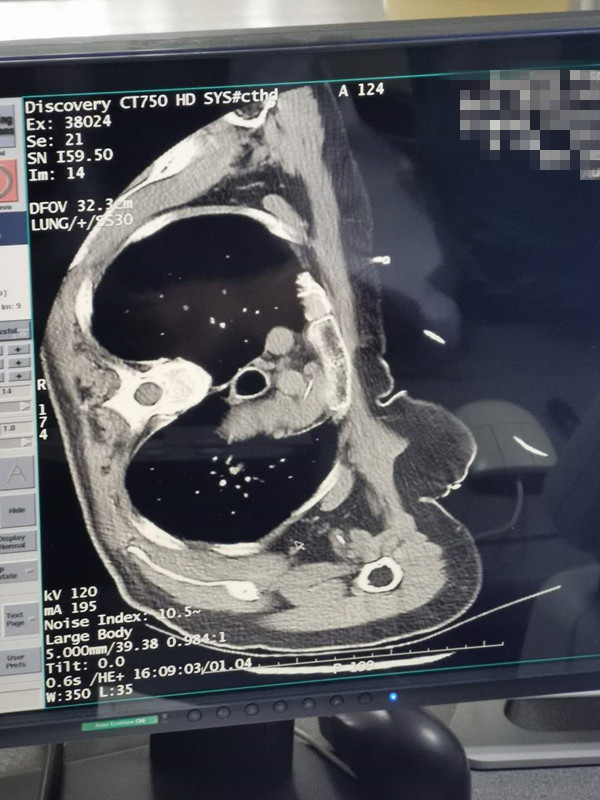

66岁肺部氩氦刀冷冻消融

发布人:美国氩氦刀技术官方网站    发布时间:2020/8/12 16:28:51